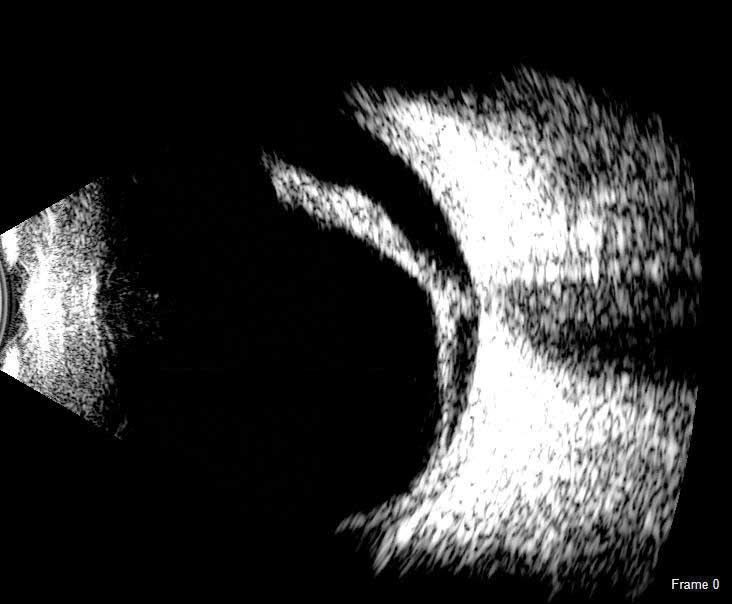

The DGH 8000 B-Scan combines the most advanced ultrasound technology available with the processing power, data storage and connectivity advantages of a personal computer. The DGH 8000 is equipped with dual 12.5 MHz and 15 MHz frequencies in the same probe, which results in a unique depth selection range from 3 cm and 6 cm in 12.5 MHz mode and 5 cm and 10 cm in 15 MHz mode.

The DGH 8000 B Scan delivers clear images for the posterior portion, even when optical clarity is compromised:

- Retinal Detachments

- Vitreous Detachments

- Vitreous Humor Pathologies

- Staphylomas

- Posterior Segment Pathologies

- Choroidal Pathologies

- Optic Nerve Pathologies

- Scleral Thickening